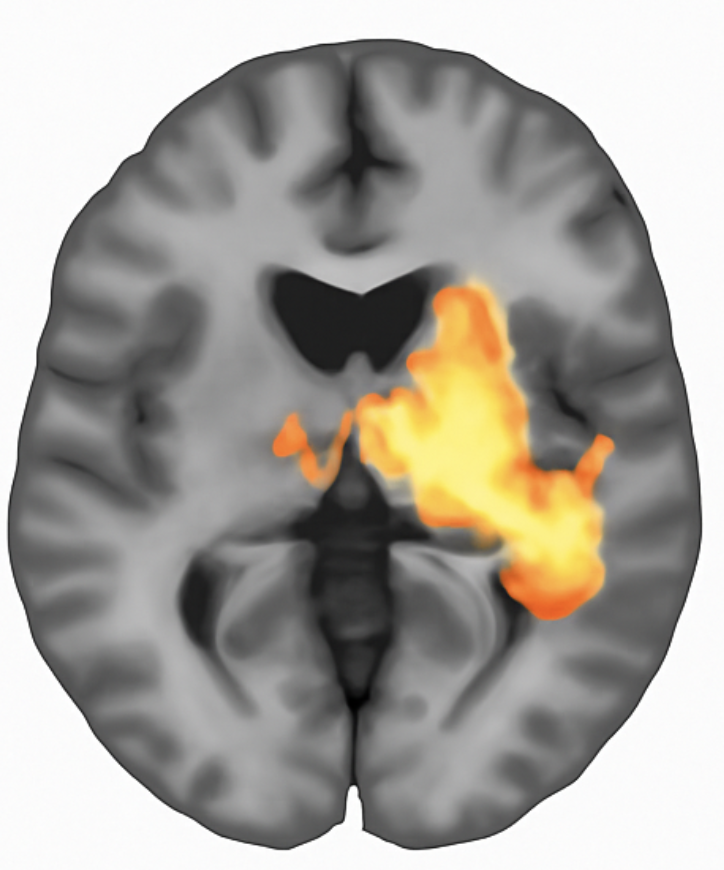

Figure 2: Activation map generated by voxelwise GLM analysis. Colored regions indicate voxels exceeding the statistical threshold (p < 0.001, uncorrected). The analysis identified 11 significant voxels representing 0.275% of the brain volume, with peak activation at coordinates [18, 16, 3] achieving t = 3.89.

The GLM output provides interpretable metrics: the number and percentage of significant voxels, cluster locations and sizes, and peak statistics with precise coordinates enabling cross-study comparison.